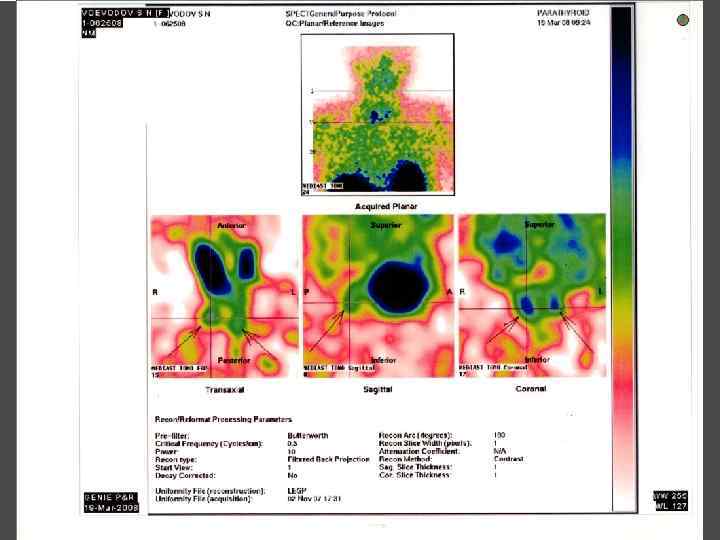

МЕТОДЫ ИССЛЕДОВАНИЯ ► Определения уровня кальция крови, паратгормона ► Сцинтиграфия паращитовидных желез с Тс99 ► УЗИ ► ПТАБ ► КТ, МРТ ► Денситометрия